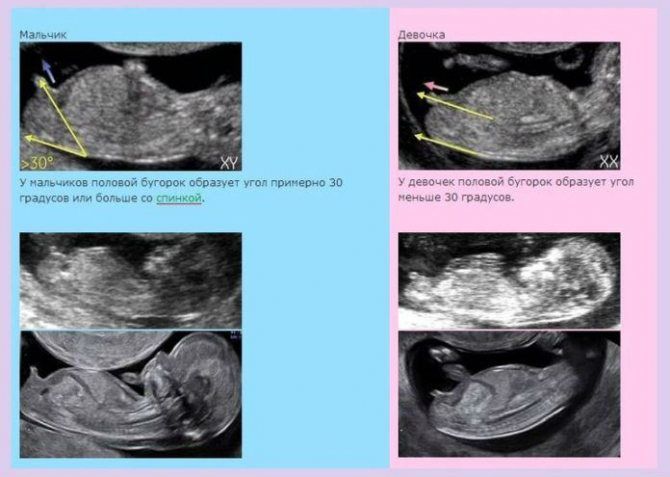

Алиса, определяют как раз таки не по писюну на таком сроке, это логично, что его там ещё нет!)), смотрят как раз по наклону бугорка, в некоторых случаях это понятно и врачи дают предположения. Мне тоже на 1м предположили пол, на 2м подтвердилось.

Алиса, вообще не правда. Половые бугорки с 12 недель более менее различимы. Даже сейчас по своим узи я вижу разницу, плюс с сыном мне на 1 скрининге уже сказали пол.

Если это бугорок, то мальчик - торчит под углом.